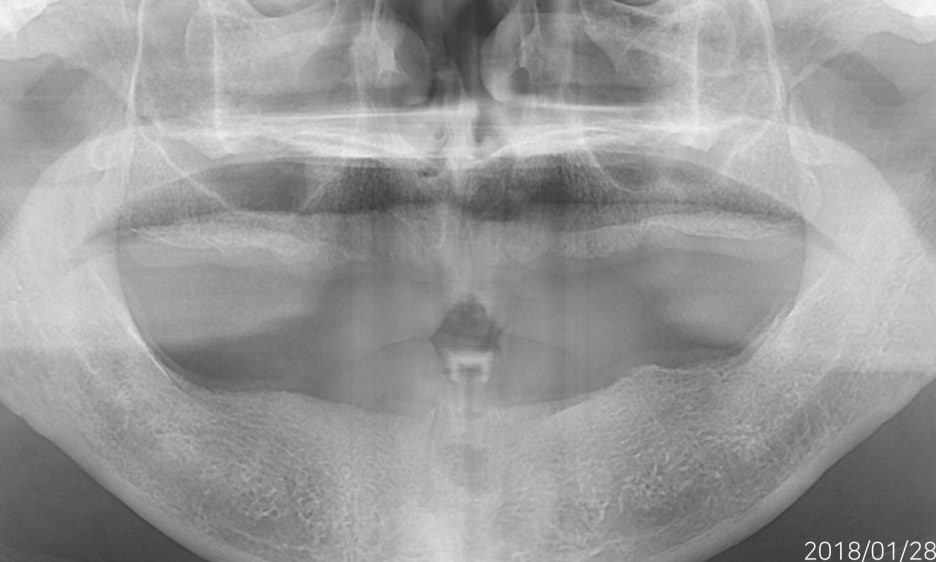

무치악환자를 위한 전악임플란트

전악임플란트 중점 치료

<참고이미지> 무치악 환자의 임플란트 치료 사례 / 환자에 따라 치료결과는 다를 수 있으며 임플란트 주위염 등이 발생할 수 있습니다.

무치악 환자에게 적용시 치아의 기능을 일정수준으로 회복할 수 있는 치료입니다.